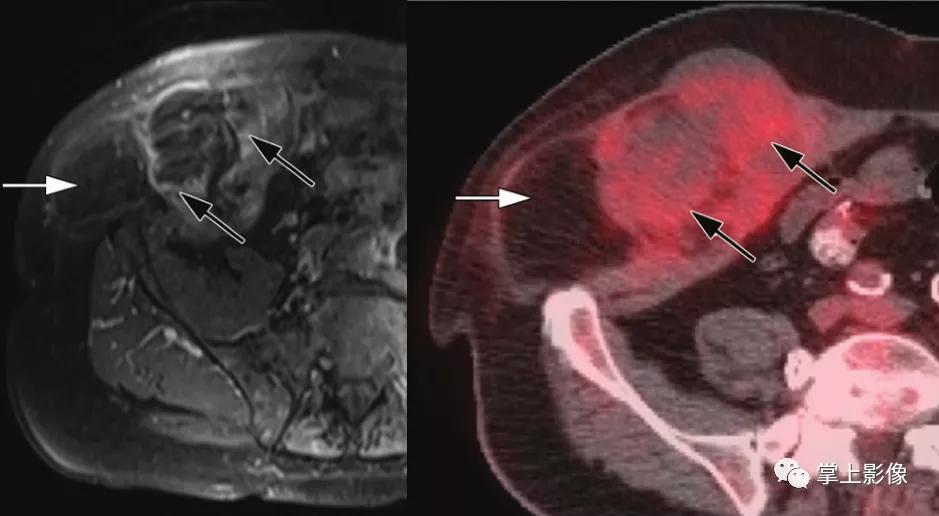

7岁男性脂肪肉瘤。轴向增强T1加权MR图像和轴向FDGPET图像示肉眼可见含脂肪肿块(白色箭头)的高代谢增强型软组织成分(黑色箭头)。活检结果证实为脂肪肉瘤